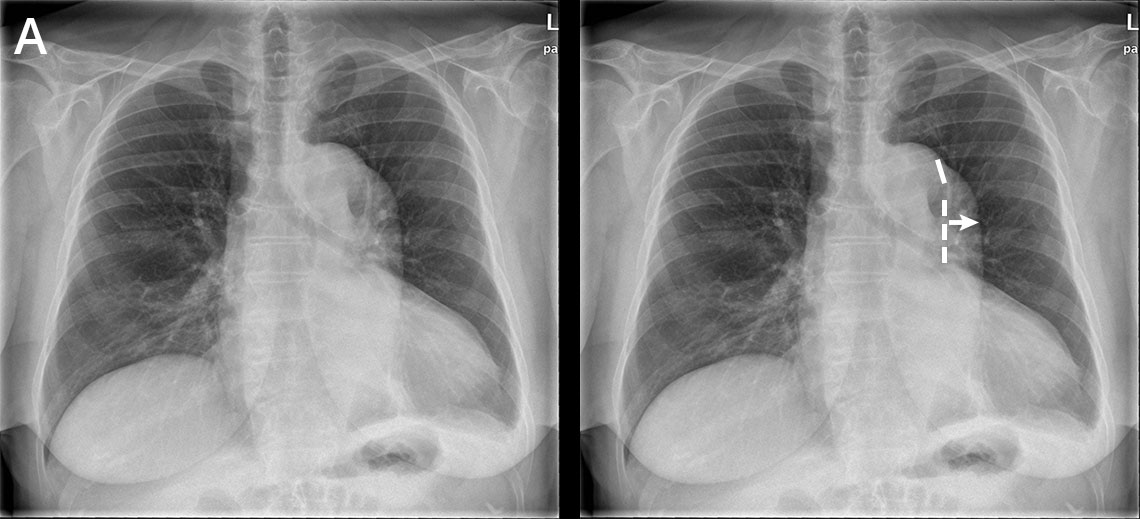

Aortan dissekoituma keuhkokuvassa (sivukuva ilman löydösmerkintöjä).

Aortan dissekoituma keuhkokuvassa (sivukuva löydösmerkinnöin).

Sivukuvassa on nähtävissä normaalia leveämpi laskeva aortta. Potilaalla oli B-tyypin aortan dissekoituma. Vasemmalla hieman pleuranestettä.